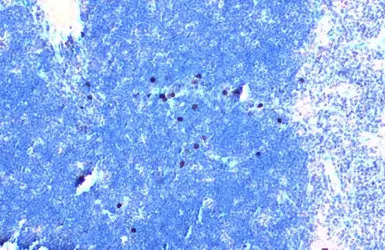

TLR3 antibody detects TLR3 protein at cytoplasm by immunohistochemical analysis.

Sample: Paraffin-embedded mouse thymus gland.

TLR3 stained by TLR3 antibody (GTX113022) diluted at 1:500.

Antigen Retrieval: Citrate buffer, pH 6.0, 15 min